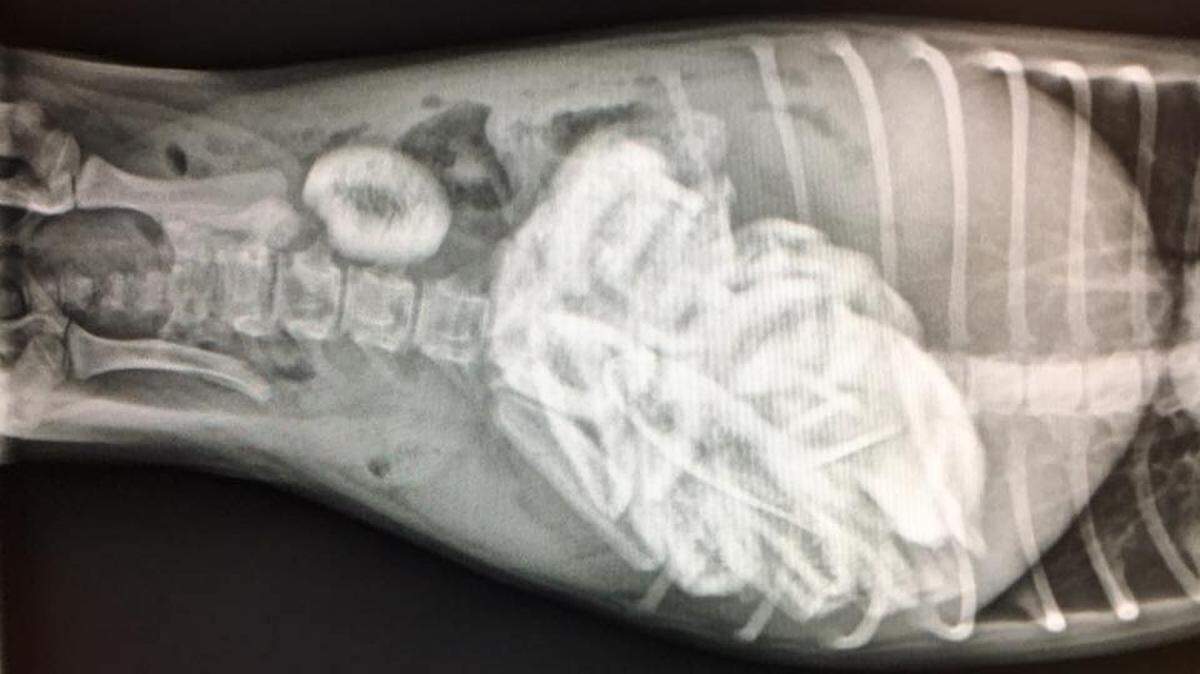

An x-ray shows the dozens and dozens of short ribs in the puppy’s stomach and intestines, which were surgically removed last week, rescuers said.

An x-ray shows the dozens and dozens of short ribs in the puppy’s stomach and intestines, which were surgically removed last week, rescuers said. Sacramento SPCA

“We kind of had a pool to, you know — how many would we find?” Dr. Laurie Siperstein-Cook, who performed the surgery, said in an interview with ABC10. “The highest guess was 22, and it turned out to be 46. And we’re going, ‘How does a little six-pound puppy eat 46 of these?’”

Siperstein-Cook said the dog weighed just six pounds.